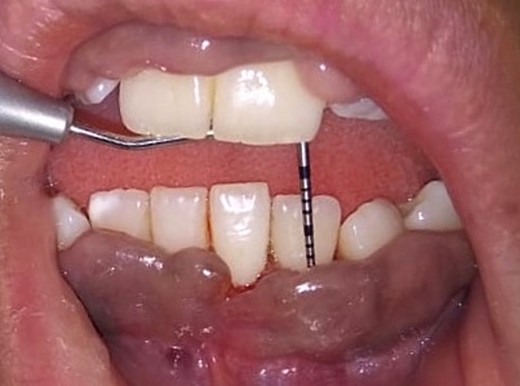

Intraoral examination shows generalized puffiness and swollen gingiva, mainly in the upper and lower anterior region covering two-third of the entire teeth, the color of the gingiva was bluish red, which bleeds on slight provocation as well as on mastication of hard food. (Fig. 1).

On the day of the procedure, a complete blood test was done which shows normal limit values. Following the administration of local anesthesia, periodontal pockets were checked (Fig. 2) and the bleeding points were marked using a Krane Kaplan pocket marker, (Fig. 3) continuous incision was made with the scalpel and blade no. 15, keeping the bevel at ~45° to the tooth surface. Once the incisions had been made, the excision of the tissue was done with a curette (Fig. 4). Further electrocautery was used as a coagulating machine to control the bleeding. Gingivoplasty, i.e. reshaping and recontouring of gingiva following the normal festooned pattern was done. Coe-Pak was placed and the patient was recalled after 1 week for check-up (Fig. 5).

Measuring the periodontal pocket of lower anteriors showing gingival enlargement.